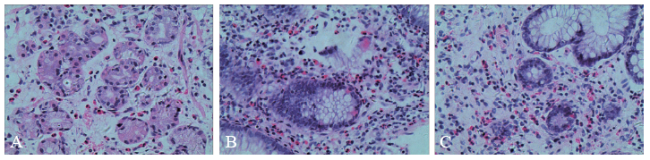

图2 一例EG患者病理活检切片(苏木素-伊红染色,×200)

A:胃底部溃疡;B:回盲部溃疡;C:结肠溃疡

X线胸片提示双肺未见异常。胃镜检查显示胃底、胃体、胃窦及十二指肠仍有多发散在溃疡,直径约0.5 ~ 0.8 cm(图1A、B),病理活组织检查(活检)提示胃黏膜呈慢性活动性炎症,固有层较多嗜酸性粒细胞浸润,约60个/高倍镜视野(图2A)。结肠镜显示回肠末段、升结肠、横结肠、乙状结肠及直肠局部黏膜充血、水肿,多发散在点、片状糜烂及溃疡,直径约0.1 ~ 1.0 cm,病变间隔有正常黏膜(图3A、B)。病理活检提示肠黏膜呈慢性活动性炎症,固有层较多嗜酸性粒细胞浸润,其中回盲部约100个/高倍镜视野,结肠约60个/高倍镜视野(图2B、C)。胶囊内镜显示小肠黏膜多发散在糜烂、溃疡灶,溃疡形状不规则,直径约0.3 ~ 0.8 cm,病变呈跳跃性,病变之间有正常黏膜(图4A)。